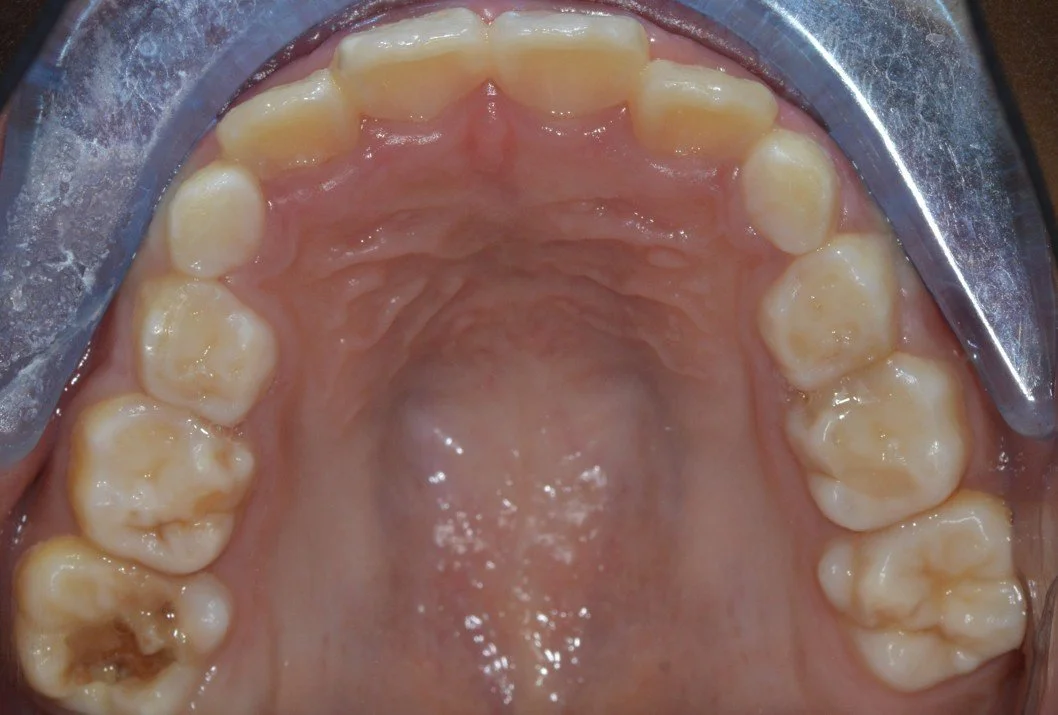

Severe hypomin with PEB: 6/46

Will Toothmousse do much here?